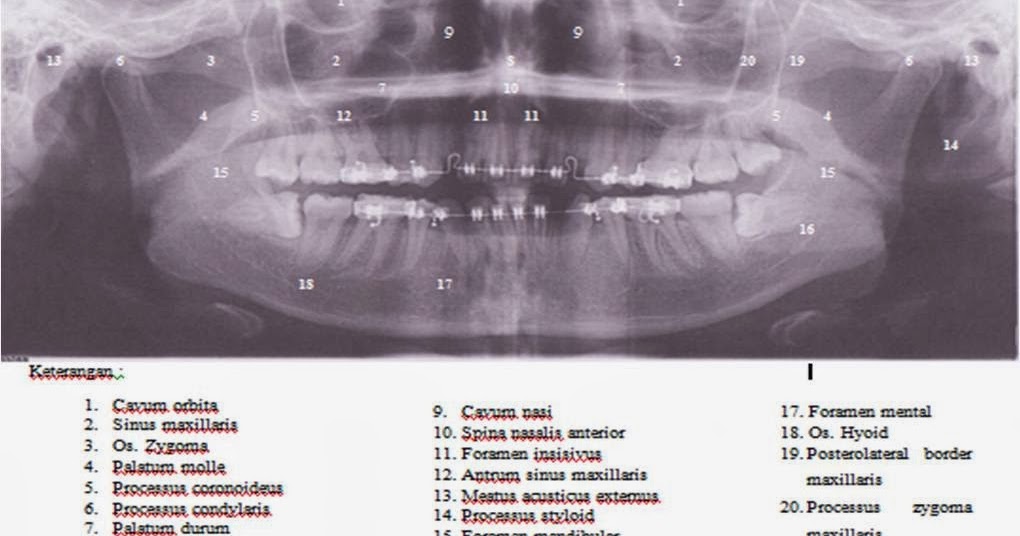

GAMBARAN ANATOMI NORMAL RADIOGRAFI PANORAMIK

GAMBARAN ANATOMI NORMAL RADIOGRAFI PANORAMIK www.scribd.com

radiografi panoramik gambaran interpretasi anatomi pemeriksaan radiograf sulung

Foto Panoramik ~ Dent-ias || Notes

Foto Panoramik ~ Dent-ias || notes dentias.blogspot.co.id

panoramik

PANORAMIK RADIOGRAFI | MANJADDA WA JADDA

PANORAMIK RADIOGRAFI | MANJADDA WA JADDA munsheed.blogspot.com

radiografi panoramik